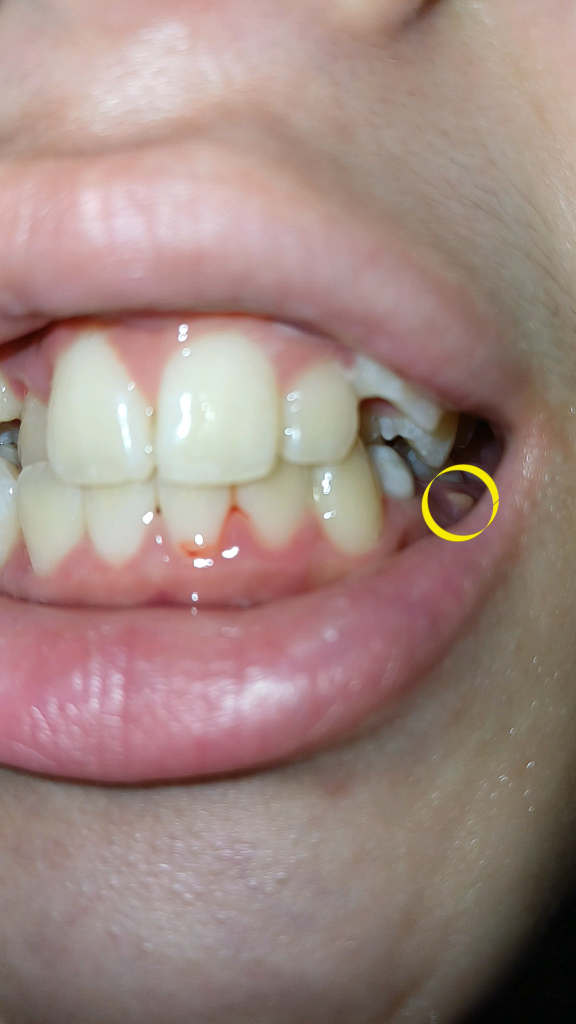

저상태라면 빨리 교정과에 가셔서 유치를 발치하고 영구치를 견인해서 맹출시키는 교정을 하셔야될것같습니다.

하지만 사진으로 봤을 경우에는 유치의 뿌리 쪽에 염증이 생겨서 고름이 차이는 것으로 보입니다.

이런 경우에는 유치를 발치를해주는 것이 좋으며 발치를 했을 때는 매복되어 있는 치아를 맹출 시키거나 보철 치료 등으로 치아가 없는 부위를 수복해 주는 것이 좋습니다.